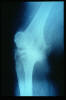

APR Gonartrosis